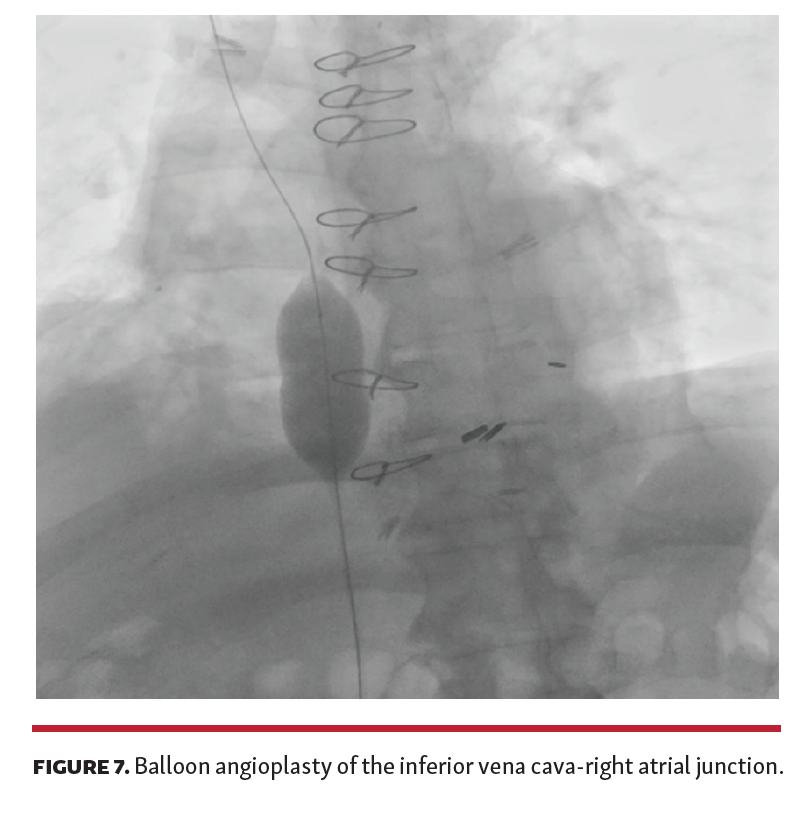

A 67-year-old man presented with new-onset abdominal pain, fullness, and lower-extremity edema approximately 2.5 years after bicaval orthotopic heart transplant from an appropriately sized donor. Cardiac allograft biventricular systolic function was normal and there was no histologic evidence of allograft rejection. Abdominal imaging revealed new findings of a nodular liver suggestive of cirrhosis, in addition to splenomegaly and ascites (Figure 1). There was no evidence of hepatic or portal vein thrombosis, nor stenosis or stricture of the inferior vena cava (IVC). Laboratory testing was notable for an elevation in bilirubin and alkaline phosphatase with negative viral hepatitis serologies.